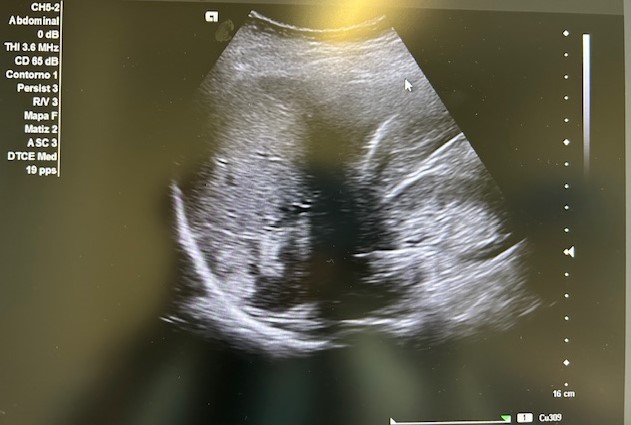

Descripción de los hallazgos ecográficos y las imágenes más relevantes para la resolución del caso

En la ecografía podemos apreciar hepatomegalia > 16 cm con múltiples imágenes en su interior hiperecogénicas sugestivas de LOE. No otros hallazgos a destacar.

El paciente fue valorado en Consultas Externas confirmando el diagnóstico. Se realiza ecografía abdominal con hallazgos de múltiples nódulos hepáticos de entre 12-35mm. En la colonoscopia, neoplasia circunferencial con aumento de consistencia, áreas ulceradas y necrosis, con estenosis incompleta, siendo compatible con adenocarcinoma de sigma.